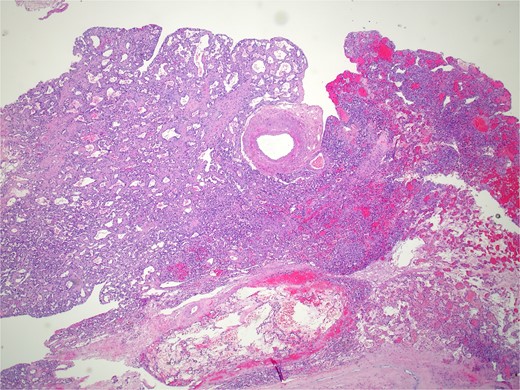

Pathology revealed a benign vascular neoplasm, whose morphological pattern favored AH (Figs 3 and 4).

Histopathology micro findings showing anastomosing proliferation of capillary-sized vessels with mild endothelial cell nuclear variability.

Histopathology micro findings showing scattered “hobnail” cells.